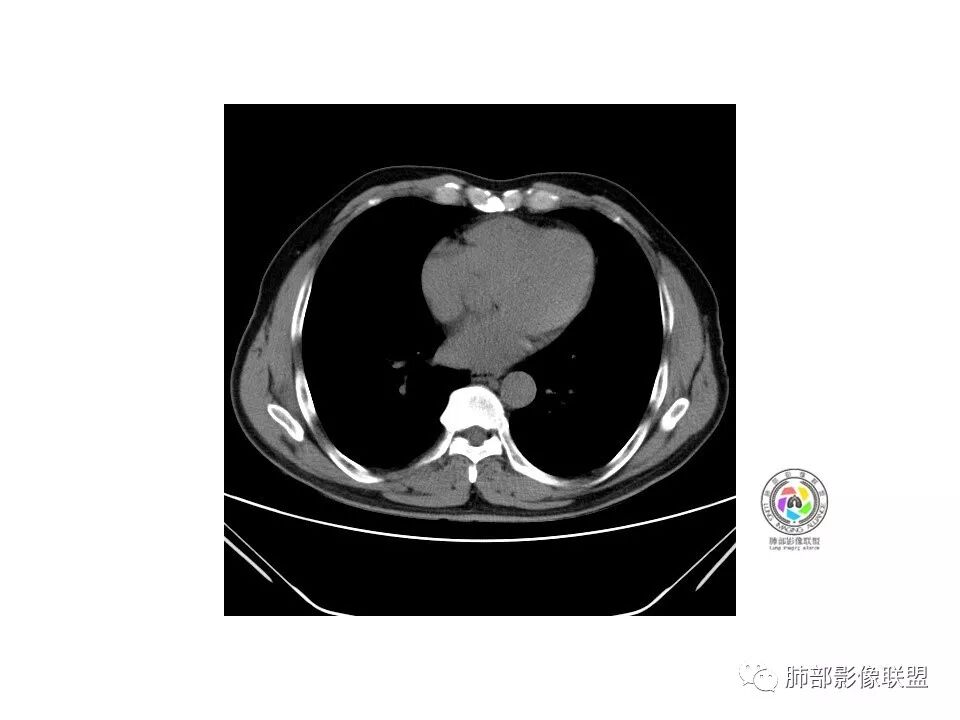

1.纵膈窗未显示;水平裂有轻微凹陷,那个条索影,有形成机理进一步分析;前方那个血管,可能是肺动脉?有一定弯曲度(向病灶),后方这个是肺静脉;3个小叶凹,有可能,受到阻挡,邻近小血管有相应改变;薄层那个细小血管有弯曲,形成部分实性;

2.大小:估计15*10mm左右;

3.CT值:混杂,有些偏高;

4.周围小血管,有形成毛刺趋势;

5.血管:如上述;

6.胸膜和叶间裂:有轻微牵拉;

诊断:浸润性腺癌;鉴别:炎性结节;

处理:炎标、肿标、病史、职业史、抽烟史,既往胸部检查;

老年男性,咳嗽咳痰3天。MGGN,边缘见月牙铲、胸膜牵拉,血管移动联通?冠状位隐约可见支气管穿行,考虑MIA,重建冠位可见结节比较靠近叶裂,可积极手术处理。